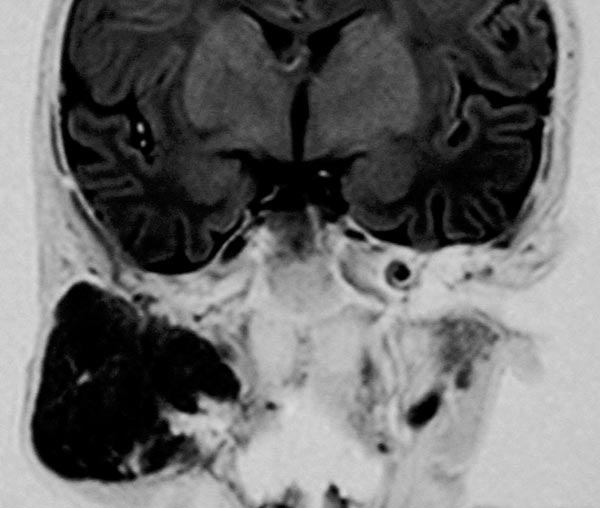

Coronal inversion recovery sequence (MRI) again shows the extent of the hemangioma very clearly. The signal intensity is isointense to the brain tissue. It is clearly a solid mass.